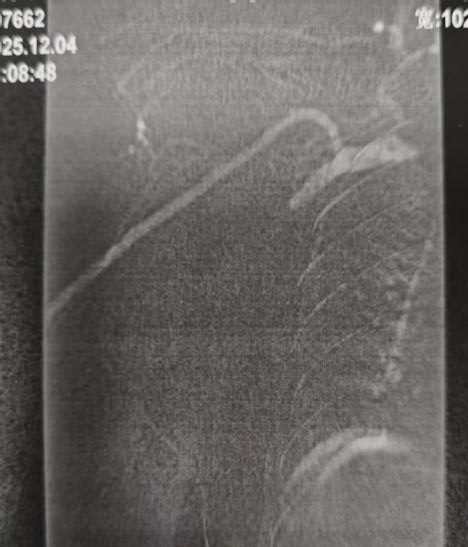

球囊扩张前造影球囊

本例患者系慢性肾脏病CKD5期规律透析患者,因上肢严重肿胀1+月就诊,经检查确诊为无名静脉闭塞。无名静脉是上肢血液回流至心脏的主要通道,其闭塞会导致上肢及头颈部静脉血液回流受阻,引发进行性肿胀、疼痛,甚至可能危及生命。面对治疗难题,肾内科血管通路团队经过周密评估,决定采用介入技术进行复合手术。